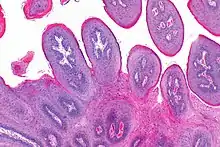

![]() | Benign cystic teratoma | Micrograph of Teratoma Ovary showing areas of cartilage, mucous glands, squamous epithelium and hair follicle. | Category: Histopathology of mature teratoma of ovary | teratoma |